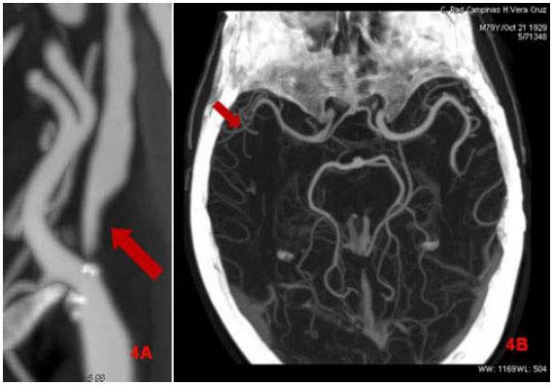

Na angio-RM intracraniana observa-se redução da arborização arterial no hemisfério correspondente,

com menor número de ramos visíveis no território da ACM. Indique a alternativa que melhor traduz

este achado: